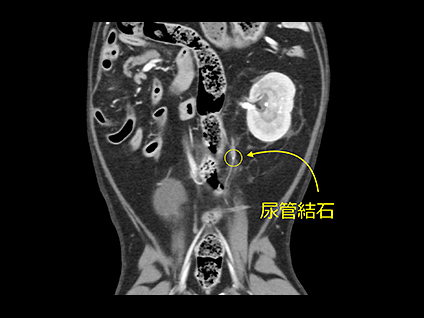

その他の疾患におけるCT検査

頭蓋内疾患(一部)、肺疾患、歯牙疾患、異物、胆道疾患そして尿路結石などにおいても迅速かつより正確な診断が可能となります。